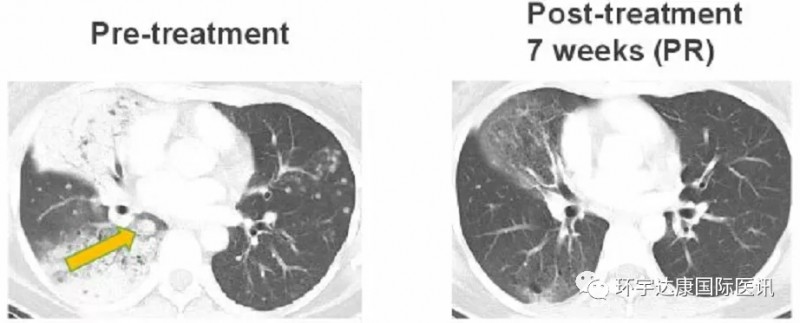

2、有效克服克唑替尼耐药

一位38岁的女士确诊为CD74-ROS1融合阳性非小细胞肺癌,之前接受过化疗和克唑替尼的治疗,但是出现了一种新的耐药突变ROS1G2032,患者接受Taletrectinib(600mg,QD)治疗,在第7周时,肺部肿瘤迅速缩小,评效为部分缓解(PR),目前该患者仍在接受治疗中。